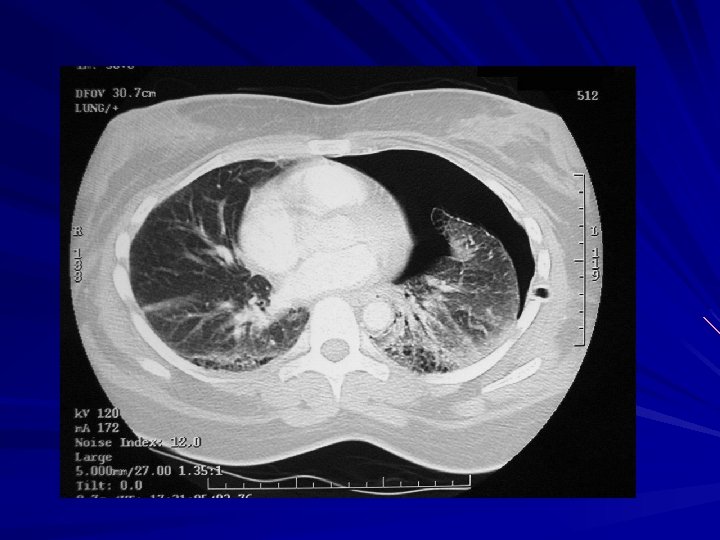

Metastatic Cancer to the lungs Multiple variably-sized masses are seen in all lung fields.